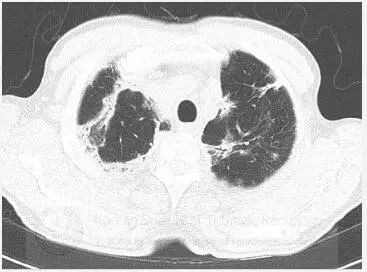

初始胸片显示双肺斑片状或外周实变,以及磨玻璃影。胸部CT显示双肺多灶性、斑片状实变,伴中央空气支气管征,以及外周磨玻璃影。病变在外周、上叶多见。

鉴别诊断:包括慢性嗜酸粒细胞性肺炎、隐源机化性肺炎和Churg-Strauss综合征。

诊断:慢性嗜酸粒细胞性肺炎

胸片常显示不呈段或叶性分布的周围片状阴影,常为双侧分布。CT显示典型的不呈段性气腔实变,以外周受累为主。不常见表现包括磨玻璃影、结节和网格影。